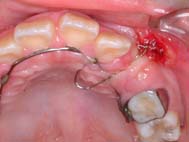

症例4:(施術基本料はAとなりますが、将来Bへ移行予定です。)

治療途中1        治療途中2        経過観察中

犬歯の埋伏歯です。赤丸の位置から牽引しました。